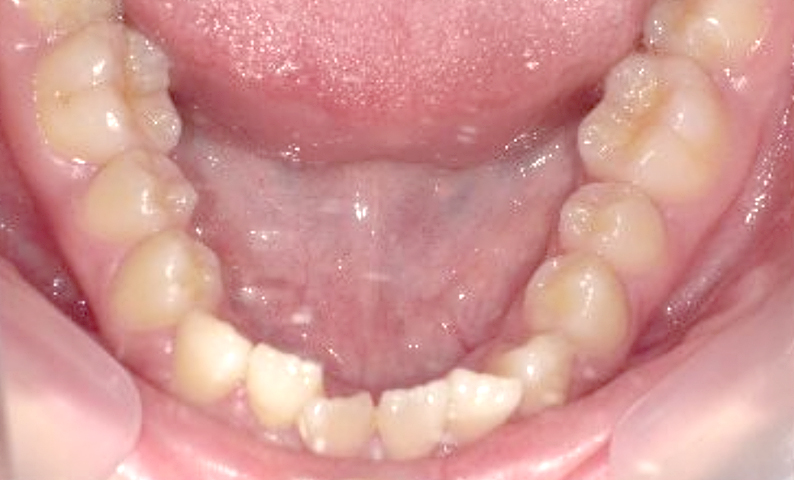

症例_004 上下顎の部分矯正

治療期間:8ヶ月金額:54万円+税女性前歯のガタガタ捻転歯